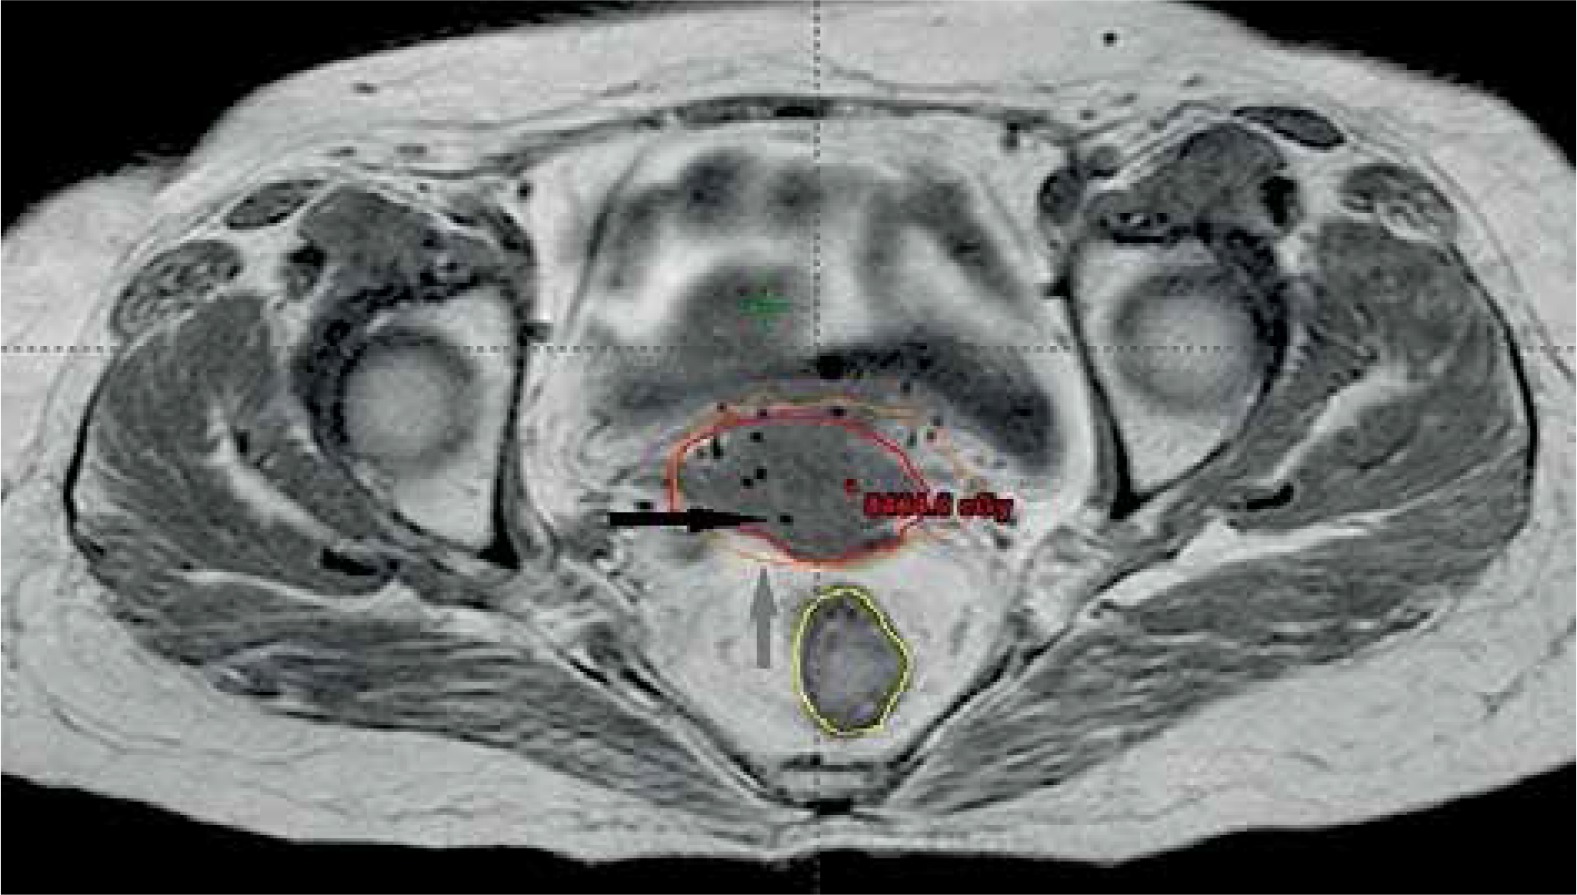

Gross tumor volume, high-risk clinical target volume (HR-CTV), intermediate-risk clinical target volume (IR-CTV), and OARs were delineated with the use of MR T2 weighted images, following GEC-ESTRO guidelines. HR-CTV delineation was challenging, as pre-brachy MR images were not available. This was overcome by changing the contrast resolution and EUA findings (Figure 1). T1 weighted images were helpful for a catheter reconstruction, and the catheters were better appreciated as black straight lines without any interruptions. Haack et al. showed that plastic catheters are well suited for MR-based reconstruction in T1 images and all catheters were visible without artifacts [9]. Depending of the extent of disease, the active lengths of the implant ranged from 6-8 cm. The dose prescribed was 20 Gy in 4 fractions (30 Gy low-dose-rate [LDR] equivalent [EQD2]) to HR-CTV, 6 hours apart, and delivered over two days. Doses of 2 cc of bladder and rectum were restricted to less than 4.0 and 3.7 Gy per fraction, respectively. With our initial experience, the dose escalation was considered to be 6 Gy per fraction. Treatment plans were performed using volumetric optimization with 5 mm dwell position (Figure 2). The OARs constraints were met using manual dragging of isodose lines. The treatment was executed using 192Ir Gammamed Plus HDR remote afterloading machine (Varian Medical Systems, Palo Alto, CA, USA), with 192Ir high activity of 10 Ci max, source of 4.6 mm active length and 0.9 mm in diameter.

In the first patient, the CT planning was performed using copper dummies to delineate the catheters. The dose-volume optimization was done in CT images, and later on MR image sequences that were acquired for planning. The identification of catheters and catheter tracking was not difficult, but the delineation of GTV was problematic due to implant geometry and contrast resolution as well as pre-treatment MR images not available. The HR-CTV delineation was completed using contrast resolution in T2 sequences and findings from clinical examination under anesthesia and to some extent, with initial CT findings. The patient comfort with plastic catheter was excellent in terms of pain.